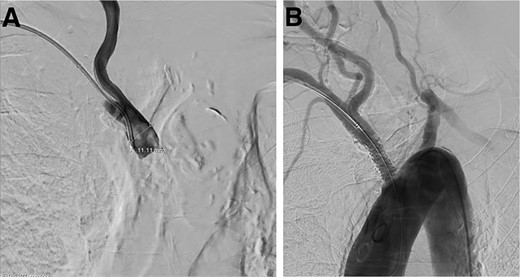

A cerebral angiogram demonstrated left common carotid occlusion (Fig. 1A) and the occlusion of the origin of the right brachycephalic trunk (Fig. 1B). Consequently, the left vertebral artery is the only cerebral vessel from the aortic arch filling anterogradely, resulting in retrograde flow to the brachycephalic trunk and of the right common carotid artery and right vertebral artery (Fig. 2A–D). The left internal carotid artery is filled from the left occipital artery, which is filled by the left vertebral artery. Intracranially the patient has the posterior communicating artery and the anterior communicating artery.

Digital subtraction angiogram demonstrating: (A) occlusion in the origin of the left common carotid artery. (B) Occlusion at the origin of the brachycephalic trunk artery.